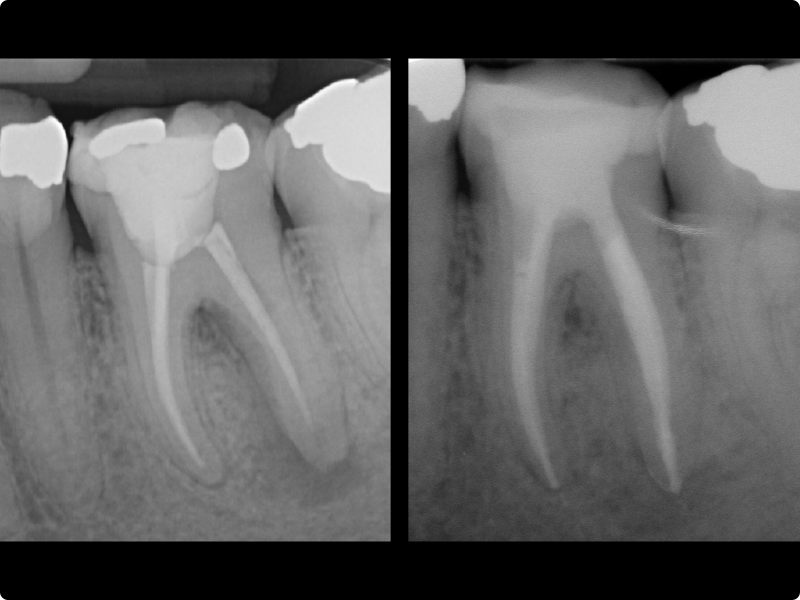

• Working length.

• Apical gauging and refinement.

• Essential protocols for canal system cleaning.

• Root canal filling: general principles.

• Endodontic seal: warm vertical condensation, carrier-based systems, bioceramic sealers.

• Apical refinement and visual gauging.

• Root canal filling using the different techniques described in the theoretical section.

• Backfilling with thermoplasticized gutta-percha.